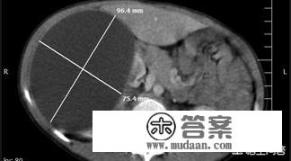

首先回答一下肾囊肿非常常见,几乎很多人都有,只是在体检的时候或者做别的检查时才偶然发现。肾脏囊肿主要分为单纯性和多囊肾,最常见的就是单纯性肾囊肿了,下图就典型的增强CT检查发现的左肾囊肿:类圆形边界清晰无强化。

CT:表现为肾内边缘锐利的圆形水样低密度灶,常突向肾外,壁薄而不能显示,可以单发或多发,累及侧或双侧肾脏;增强检査,病变无强。单纯性囊肿偶可发生出血、感染和钙化而成为复杂性囊肿,表现囊壁增厚、钙化和囊内密度增高。